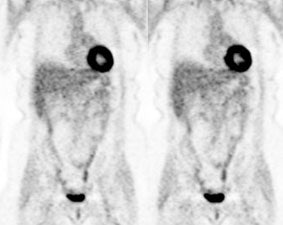

Head and neck activity: The images below show typical uptake in the tonsils (black arrows), submandibular glands (blue arrows), and parotid glands (red arrows) |

|

|